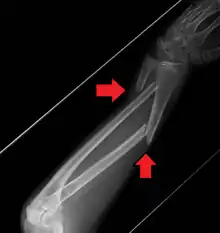

A fracture of the forearm can be classified as to whether it involves only the ulna (ulnar fracture), only the radius (radius fracture), or both radioulnar fracture.